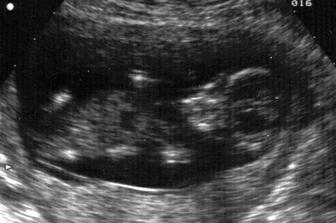

Pupíček se klube na svět

Snažit jsme se začali v září 2006, protože jsme chtěli spíše letní dítko. Hlavně aby nemělo narozeniny jako oboje rodiče v zimě... A protože člověk míní a život mění, jindy to snad ani vyjít nemohlo a čekáme dalšího Ježíška. Ve chvíli, kdy mě chtěl začít pan doktor léčit a předepsal mi prášky, rázem už nebyly potřeba. Ani jsem je nestačila začít brát. Pupíček by měl přijít na svět v půlce prosince, ale věřím, že když už se to takhle povedlo, vydrží s premiérou minimálně přesně na Vánoce 🙂